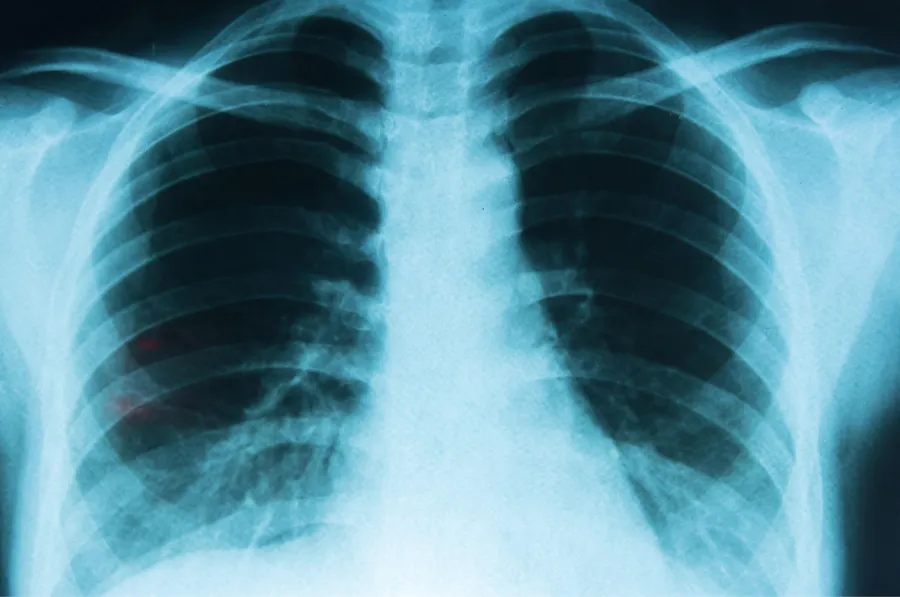

El cáncer de pulmón es uno de los tumores más frecuentes, del que se diagnostican más de 12.000 casos nuevos al año en Argentina. Su elevada mortalidad se asocia principalmente a un diagnóstico tardío, ya que en más del 50% de los casos la enfermedad se detecta en fases avanzadas, cuando ya no es operable.

El cáncer de pulmón es uno de los tumores más frecuentes, del que se diagnostican más de 12.000 casos nuevos al año en Argentina. (Infobae)